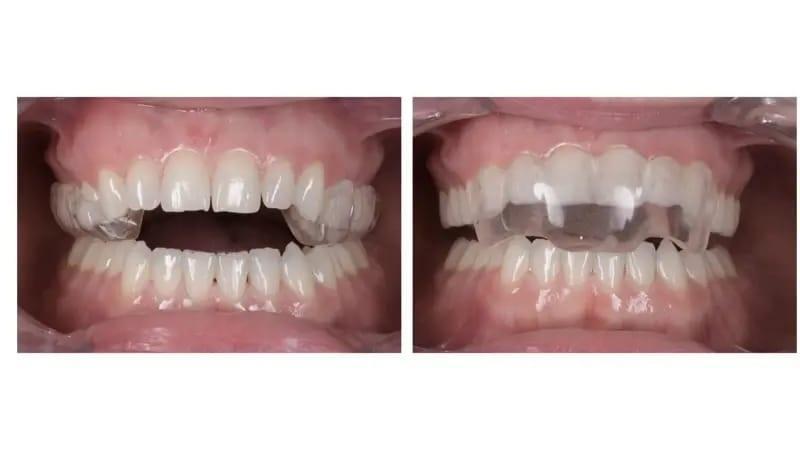

Была выбрана сплинт-шина, состоящая из двух частей, ее можно носить 24 часа в сутки в заднем сегменте днем и в переднем сегменте ночью (фото 23). Лечение шинами продолжалось в течение четырех месяцев, в течение которых было достигнуто стабильное положение мыщелков, пациентка добилась одномоментного закрывания рта и была достигнута полная ремиссия симптомов ВНЧС. В результате ротации нижней челюсти изменился прикус, что привело к увеличению переднего открытого прикуса (фото 24), увеличенное горизонтальное перекрытие верхних и нижних передних зубов (фото 25) и улучшение челюсти до классификации II класса (фото 26).

Фото 23a-b: Cплинт-шина, состоящая из двух частей. Задний сегмент (a). Передний сегмент (b).